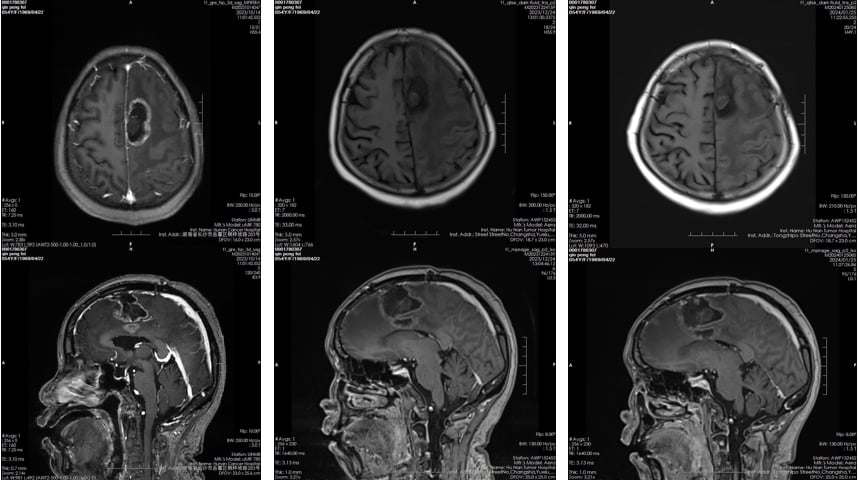

然而,经过数月治疗,患者的病情出现进展。面对这一挑战,医生调整了治疗策略,在继续使用替莫唑胺的基础上,联合应用了化疗药物替尼泊苷。患者接受了“替尼泊苷+替莫唑胺”联合方案共4个疗程的治疗。

治疗结果令人鼓舞。后续的脑部MR检查显示,术区肿块及周边水肿均较前缩小,疗效评估为部分缓解(PR)。这表明,联合替尼泊苷的二线方案成功地控制了肿瘤的进展。

图2. 使用替尼泊苷联合方案前后脑MR对比(左:联合治疗前;中、右:联合治疗后)